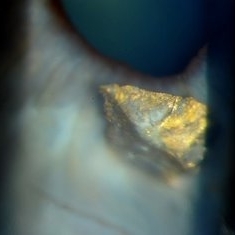

Metal Foreign Body

Jul 13 2013 by Jason S. Calhoun

Patient was welding and piece of metal ricochet into his eye. Slit lamp shows metal foreign body lodged into the iris at 6-o'clock. Patient went to surgery to have foreign body removed.

Photographer: Jason S. Calhoun, Department of Ophthalmology, Mayo Clinic Jacksonville, Florida

Imaging device: TOPCON D-90 SL NIKON CAMERA

Condition/keywords: intraocular foreign body